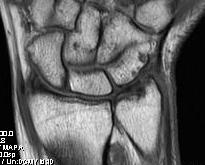

Ulno-carpal abutment

Ulnocarpal abutment and lunate chondromalacia

Ulna positive with ulnocarpal osteoarthritis

Central TFCC tear with ulna positive variance an ulnocarpal abutment on MRI

Background

Ulna impaction syndrome / Ulno-carpal abutment

Progression of wear

- TFCC thinning

- ulna head and lunate cartilage wear

- TFCC perforation

- lunate-triquetral ligament injury

- ulnocarpal osteoarthritis

Usually associated with ulna positive variance and treated with ulna shortening